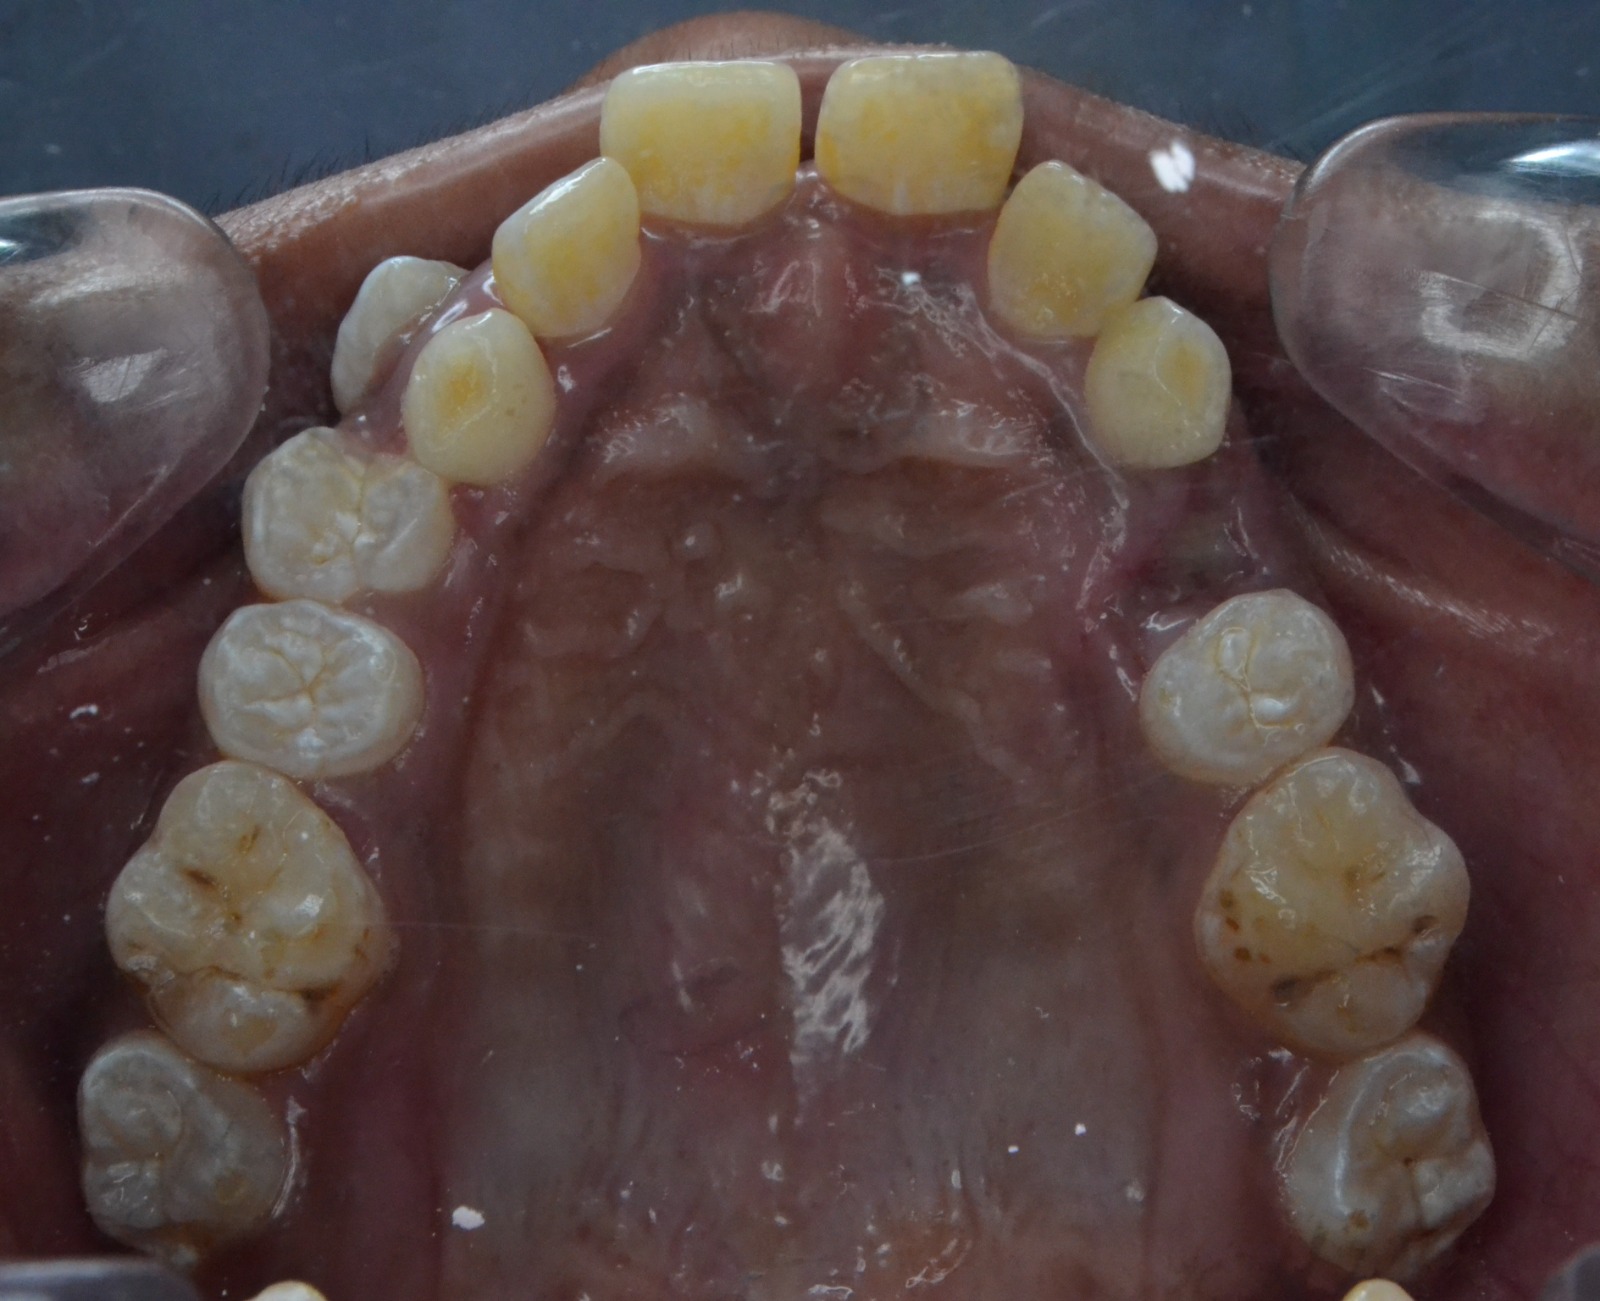

After/Before

See stunning smile transformation before and after

Before After